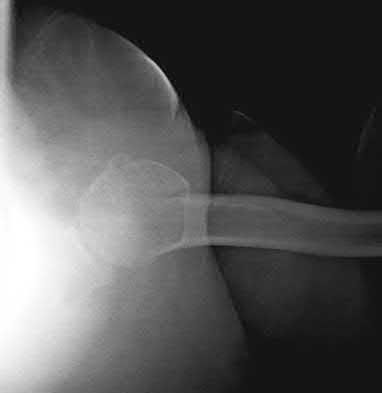

The image shows a reverse obliquity intertrochanteric hip fracture.

According to the referenced article by Haidukewych et al, unstable peritrochanteric hip fractures have a worse outcome (failed in 9/16 cases) if treated with a sliding hip screw. Two additional factors that were found to have a strong correlation with postoperative failure (nonunion, loss of reduction) were poor reduction and poor implant placement. In this study, fixed angle devices were superior. Intramedullary fixation has the added advantage of a shorter lever arm and less potential for fracture collapse and limb shortening.

The IMN also acts as a medial buttress.

According to Sanders et al, the dynamic condylar screw (DCS) can also be used in subtrochanteric models, but should not be used if extensive comminution is seen, as they reported a high failure rate with DCS in these fractures if highly comminuted. They report a 77% overall union rate with this device.